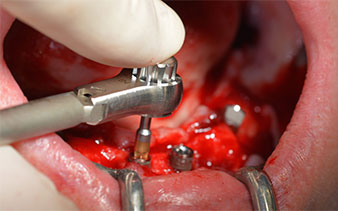

Angled abutments (35°) were screwed in to compensate for the divergence of the distal implants, with the result that the emergence profile of all implants was as perpendicular as possible to the bite plane. This is a prerequisite for occlusal placement of the provisional and subsequently the permanent denture (Fig. 15 and 16).